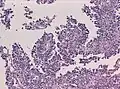

Менинготелиоматозная менингиома состоит из мозаикоподобно расположенных клеток с овальным или округлым ядром, которые содержат умеренное количество хроматина. Строма опухоли представлена немногочисленными сосудами и тонкими тяжами соединительной ткани, которые окаймляют клеточные поля. Характерны концентрические структуры из наслаивающихся одна на другую уплощённых опухолевых клеток. Центр новообразования часто обызвествлён[3].

Фиброзная менингиома состоит из фибробластоподобных клеток, которые располагаются параллельно друг другу и складываются в переплетающиеся между собой пучки, содержащие соединительнотканные волокна. Ядра вытянутые. Могут встречаться концентрические структуры и псаммомные тельца[3].

Переходная менингиома включает элементы менинготелиоматозной и фиброзной менингиом[3].

Псаммоматозная менингиома содержит большое количество псаммомных телец[3].

Ангиоматозная менингиома обильно васкуляризирована, содержит большое количество кровеносных сосудов[7].

Микрокистозная менингиома содержит большое количество микрокист, окружённых опухолевыми клетками звёздчатой формы[8].

Секреторная менингиома является редким гистологическим вариантом данного новообразования. Для неё характерна секреция веществ, которые формируют гиалиновые включения[9].

Менингиомы с обилием лимфоцитов по определению содержат большое количество включений лимфоцитарных масс.

Для метапластических менингиом характерна метаплазия (трансформирование) менинготелиальных клеток в клетки другого типа (к примеру, адипоциты)[10].